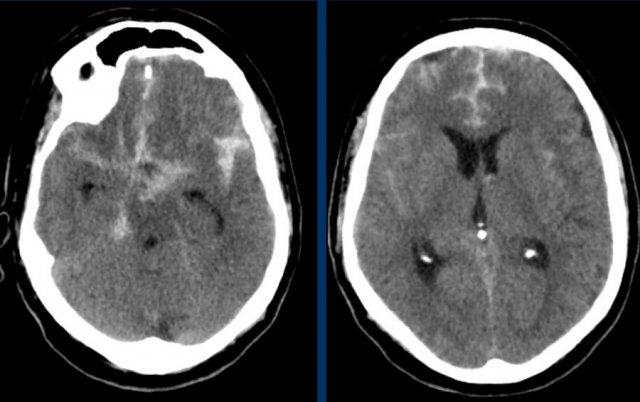

Bệnh nhân này nhập viện với não úng thủy do xuất huyết não thất (hình bên trái).

Lưu ý vùng tăng tỷ trọng rất nhỏ tại đồi thị trái, là điểm khởi phát của xuất huyết.

Theo dõi một ngày sau (hình bên phải).

Bệnh nhân được phẫu thuật đặt dẫn lưu não thất để điều trị não úng thủy.

Lưu ý đồi thị bên trái giảm tỷ trọng với ổ tăng tỷ trọng dai dẳng ở vị trí trong.

Bệnh nhân này nhập viện vì đau đầu kéo dài bốn ngày và cứng gáy do kích thích màng não.

Hình ảnh NECT cho thấy máu tăng tỷ trọng trong khoang dưới nhện.

Có một túi phình động mạch thông trước (mũi tên).

Túi phình có tỷ trọng cao, chúng tôi cho rằng đó là huyết khối bên trong túi phình.

Điều này có nghĩa là trên DSA, kích thước thực của túi phình có thể trông nhỏ hơn.

Đây là một ví dụ về xuất huyết dưới nhện trên NECT.

Lưu ý vị trí máu chủ yếu xung quanh thân não và trong não thất III và IV.

Thông thường, vị trí của máu dưới nhện giúp định hướng xác định vị trí của túi phình động mạch.

Bước tiếp theo là thực hiện chụp CT mạch máu (CTA) để tìm kiếm túi phình động mạch là nguyên nhân gây SAH.

Bệnh nhân này có túi phình tại nguyên ủy của động mạch tiểu não sau dưới trái (PICA).

Cũng cần lưu ý tình trạng não úng thủy.